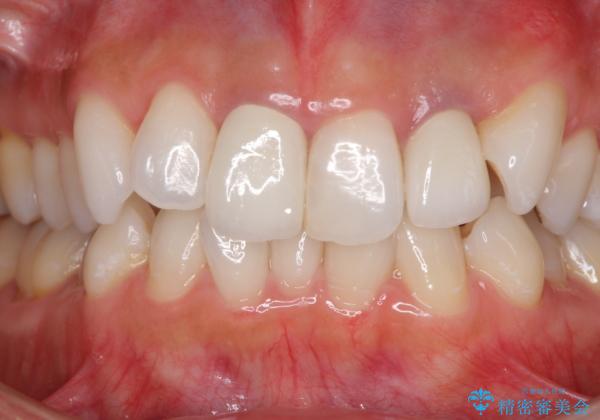

- 20年ほど前に被せた前歯のメタルボンドクラウンの色合いを気にして来院された患者様です。

2歯をオールセラミッククラウン(ジルコニアクラウン)にて補綴することとしました。

裏打ちが金属の場合、どうしても金属色を遮蔽しないとならないため、透明感のない色合いとなってしまいます。

土台の金属はグラスファイバーを含有したものに、クラウンの土台は強化セラミックとすることで、自然な前歯に仕上がりました。